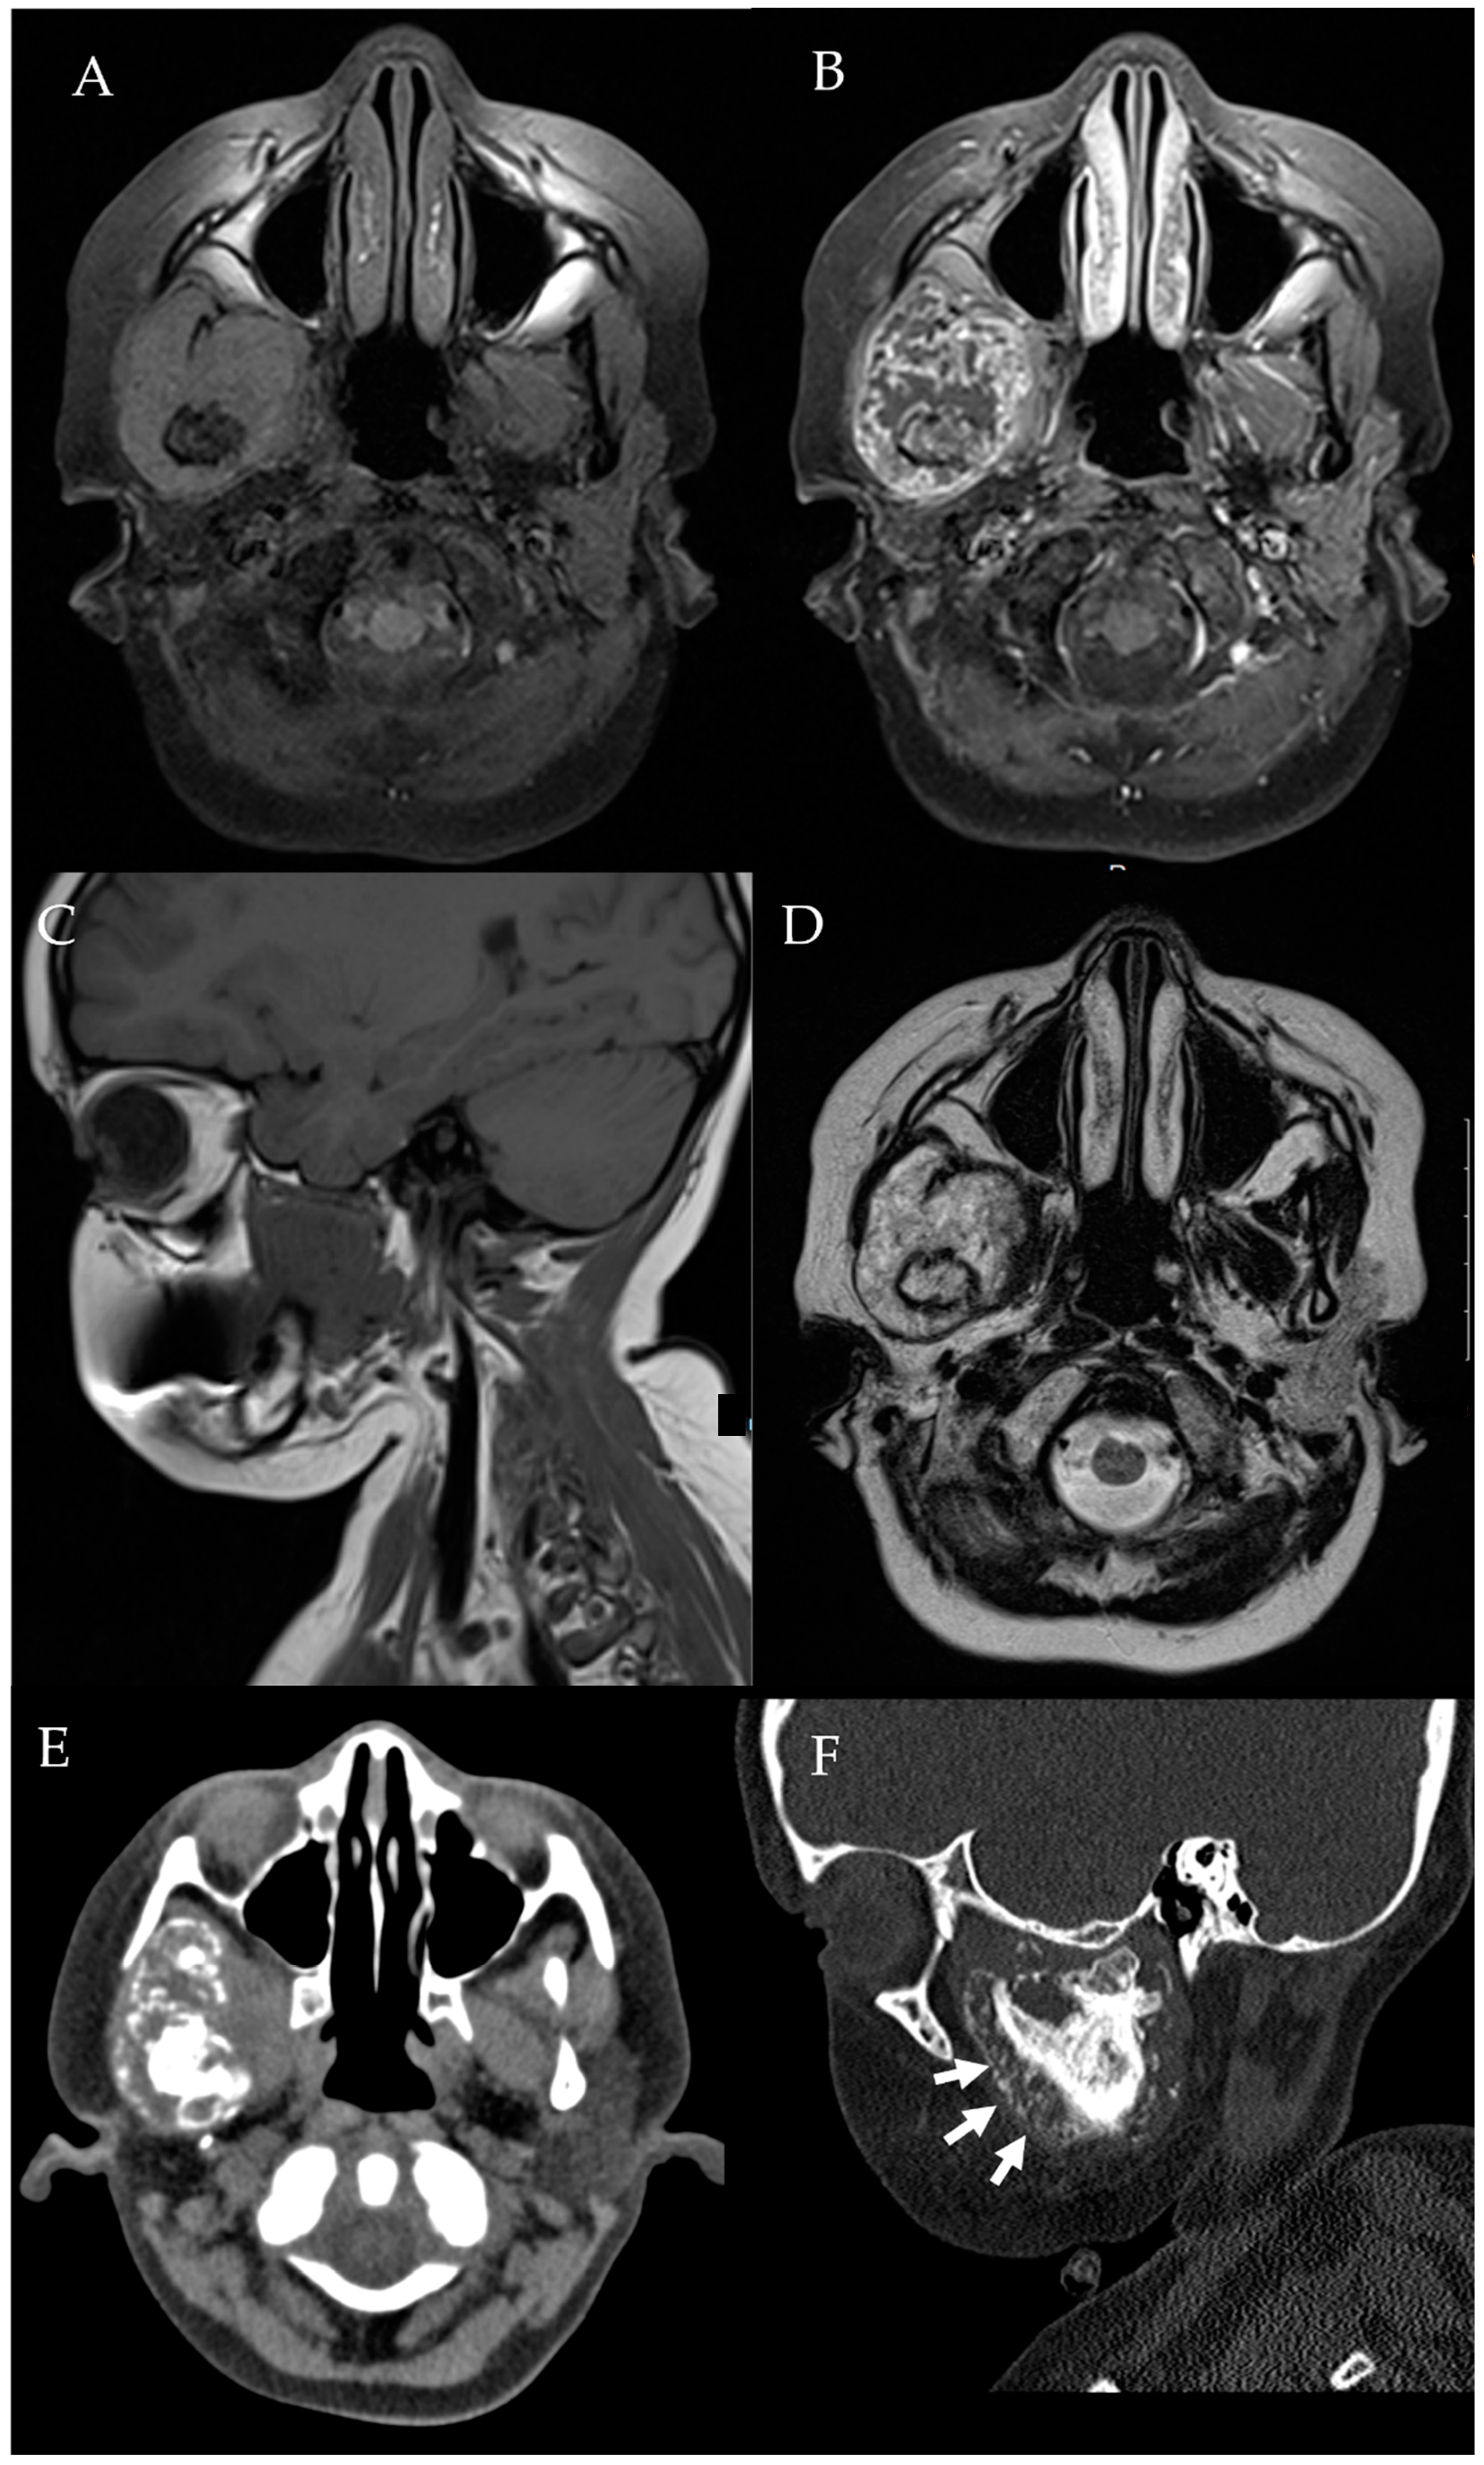

Figure 11. Condylar chondroblastic osteosarcoma. Axial pre-contrast (A) and post-contrast T1W (B), sagittal pre-contrast T1W (C), and axial T2W (D) images demonstrate a heterogeneously enhancing and T2-hyperintense right condylar mass in a nine-year-old patient. Axial (E) and sagittal (F) CT images show a soft tissue mass with mineralized matrix and aggressive periosteal reaction (small arrows) at the TMJ. Biopsy confirmed chondroblastic osteosarcoma.

Osteosarcoma is a malignant bone tumor arising from the osteogenic mesenchymal matrix and producing osteoid, fibrous, cartilaginous, and osseous tissue. It usually involves the long bones but rarely involves the jaw and is called gnathic osteosarcoma. Jaw osteosarcoma is not as aggressive as osteosarcoma in the long bones, with the mean age of patients being 35 years–10 years younger than long bone osteosarcoma. In addition, there is a male predilection, with the male-to-female ratio of 2:1 [14,49]. Radiographically, osteosarcoma can have a lytic, sclerotic, or mixed appearance with malignant periosteal reaction. On MRI, osteosarcoma resembles chondrosarcoma, presenting as a heterogeneously enhancing, intermediate T1 and high T2 signal mass (Figure 11). However, on CT or radiographs, osteosarcoma usually does not show typical ring-and-arc or whorl shape calcifications.